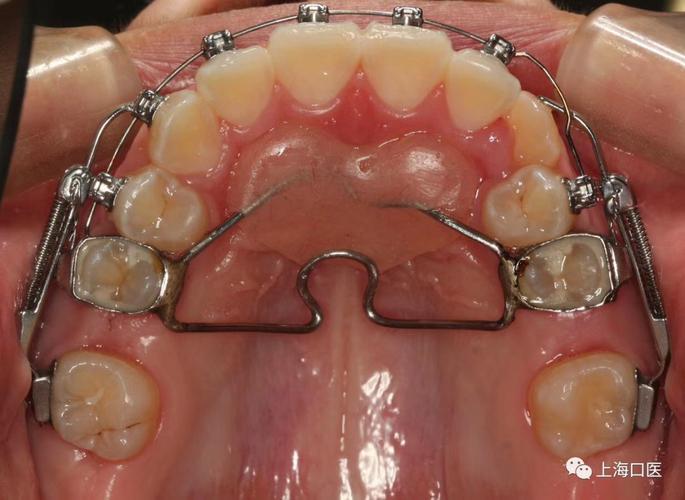

磨牙后推的矫治装置多样,根据作用方式可分为机械力装置与磁力装置两大类,各有特点与适用场景,为更直观理解,以下通过表格对比常见装置的类型、原理、优缺点及适用情况:

| 机械滑动杆装置 | 摇杆式矫治器(Jig Appliance) | 利用不锈钢丝与托槽形成的滑动杆结构,通过弹性结扎或螺旋弹簧提供持续远中移动力 | 结构相对简单,成本较低,技术成熟 | 对支抗要求高,需配合强支抗(如种植钉) | 上颌磨牙后推,尤其适用于第二磨牙未萌出的青少年 |

| 螺簧式装置 | 推簧(Open-coil Spring) | 将镍钛螺旋簧放置于磨牙与前磨牙托槽之间,通过螺簧的持续弹力推动磨牙远中移动 | 加力方式灵活,力量可调,临床操作简便 | 支抗控制难度大,易导致前牙唇倾或支抗丧失 | 下颌磨牙后推,或需配合颌间牵引的患者 |

| 磁力装置 | 钐钴磁体(Sm-Co Magnet) | 利用两块异性磁体间的磁力相互作用(一块粘接在磨牙,另一块粘接在支抗牙上)提供持续轻力 | 力量持续稳定,无需频繁调整,患者舒适度高 | 装置体积较大,成本较高,磁体可能退磁 | 对疼痛敏感的患者,或需长期轻力移动的成人 |

| 种植体支抗装置 | 微型种植钉(Micro-implant) | 将钛种植钉植入牙槽骨,作为绝对支抗,通过拉簧或弹性链直接作用于磨牙实现远中移动 | 支抗控制精准,磨牙移动效率高,不受患者合作度影响 | 需手术植入,存在种植钉松动、感染等风险 | 支抗不足或需大幅度磨牙移动的复杂病例 |